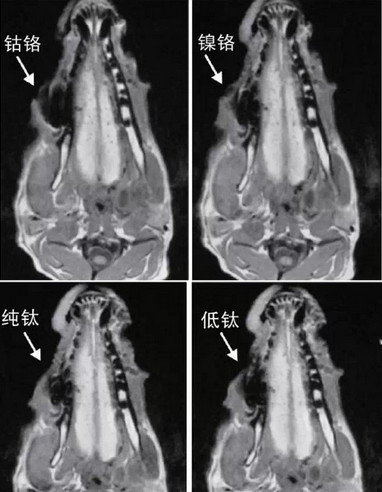

賤金屬對於(yu) 核磁共振的影響主要是如果是與(yu) 口腔相鄰部位的檢查時,可能在成像時生成偽(wei) 影(一般影響越大,偽(wei) 影越大),這對於(yu) 醫生專(zhuan) 業(ye) 判斷會(hui) 有一定的影響,但是至於(yu) 是否需要拆卸烤瓷牙後做檢查,目前也不一定,這是需要專(zhuan) 業(ye) 的工作人員才能確定的,建議檢查之前的提前和醫生溝通一下。